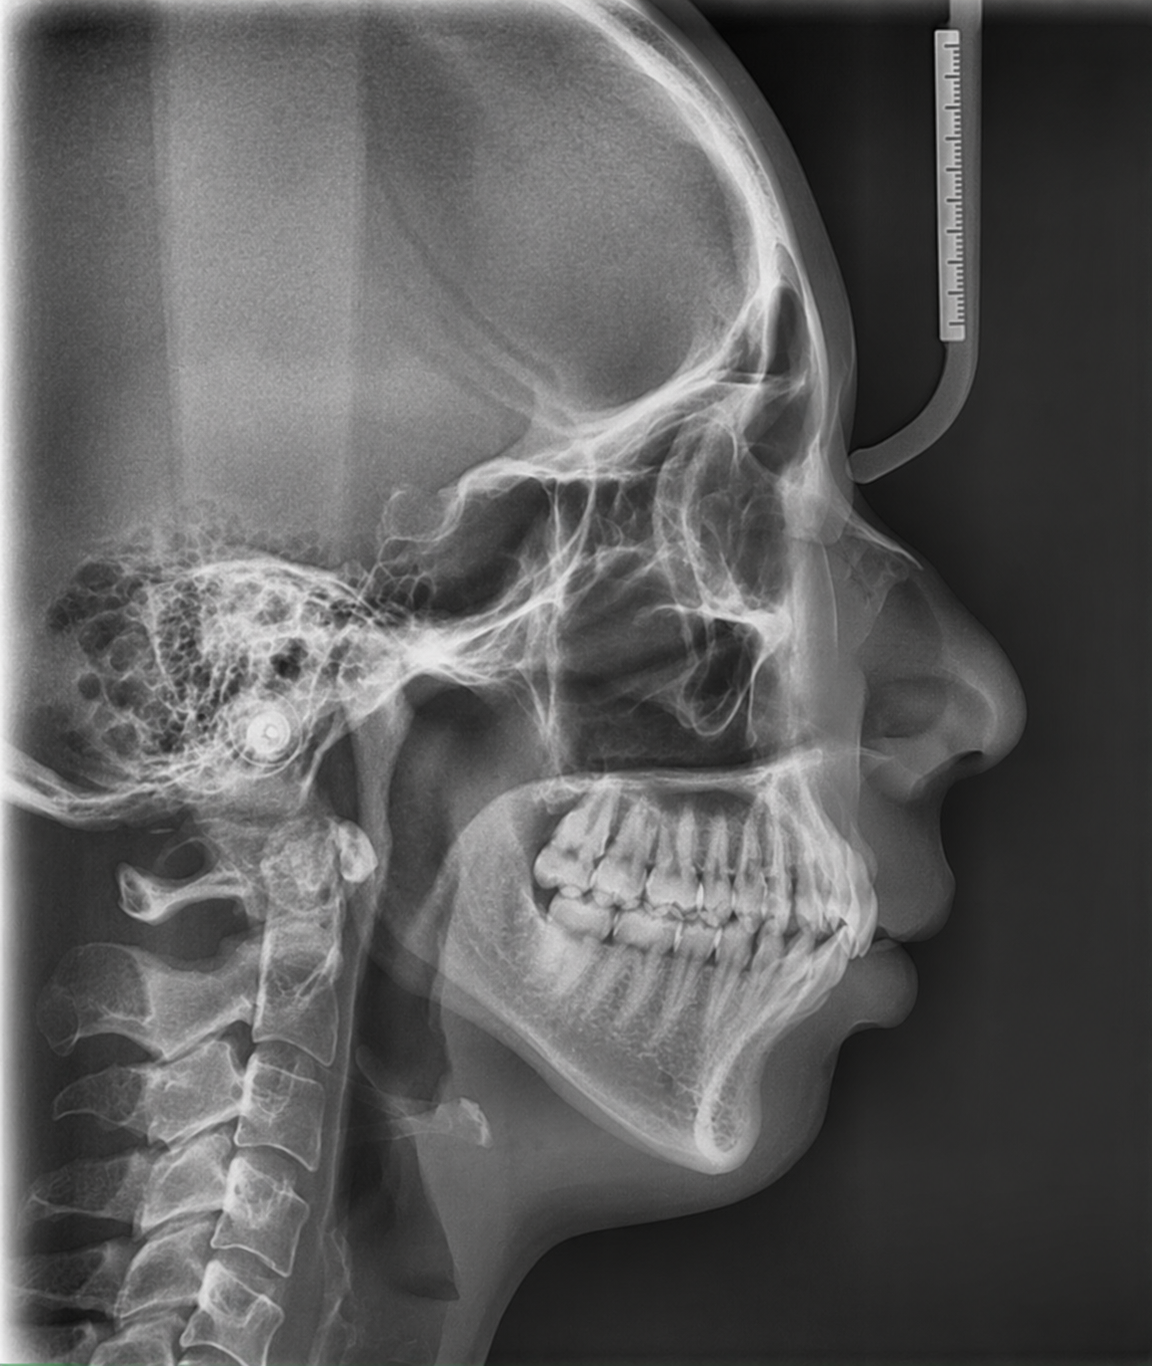

数値で分析、根拠ある診断

セファロ(頭部X線規格写真)で顎の位置を精密に計測。 感覚ではなく、数値に基づいた診断を行います。

Cephalometric Analysis

歯並びではなく、

"顎の位置"を

見ています

見た目の違和感は、骨格のズレから始まります

多くの矯正治療が「歯の位置」だけを調整するのに対し、当院は顎骨格のズレをセファロ分析で精密に把握してから治療計画を立てます。